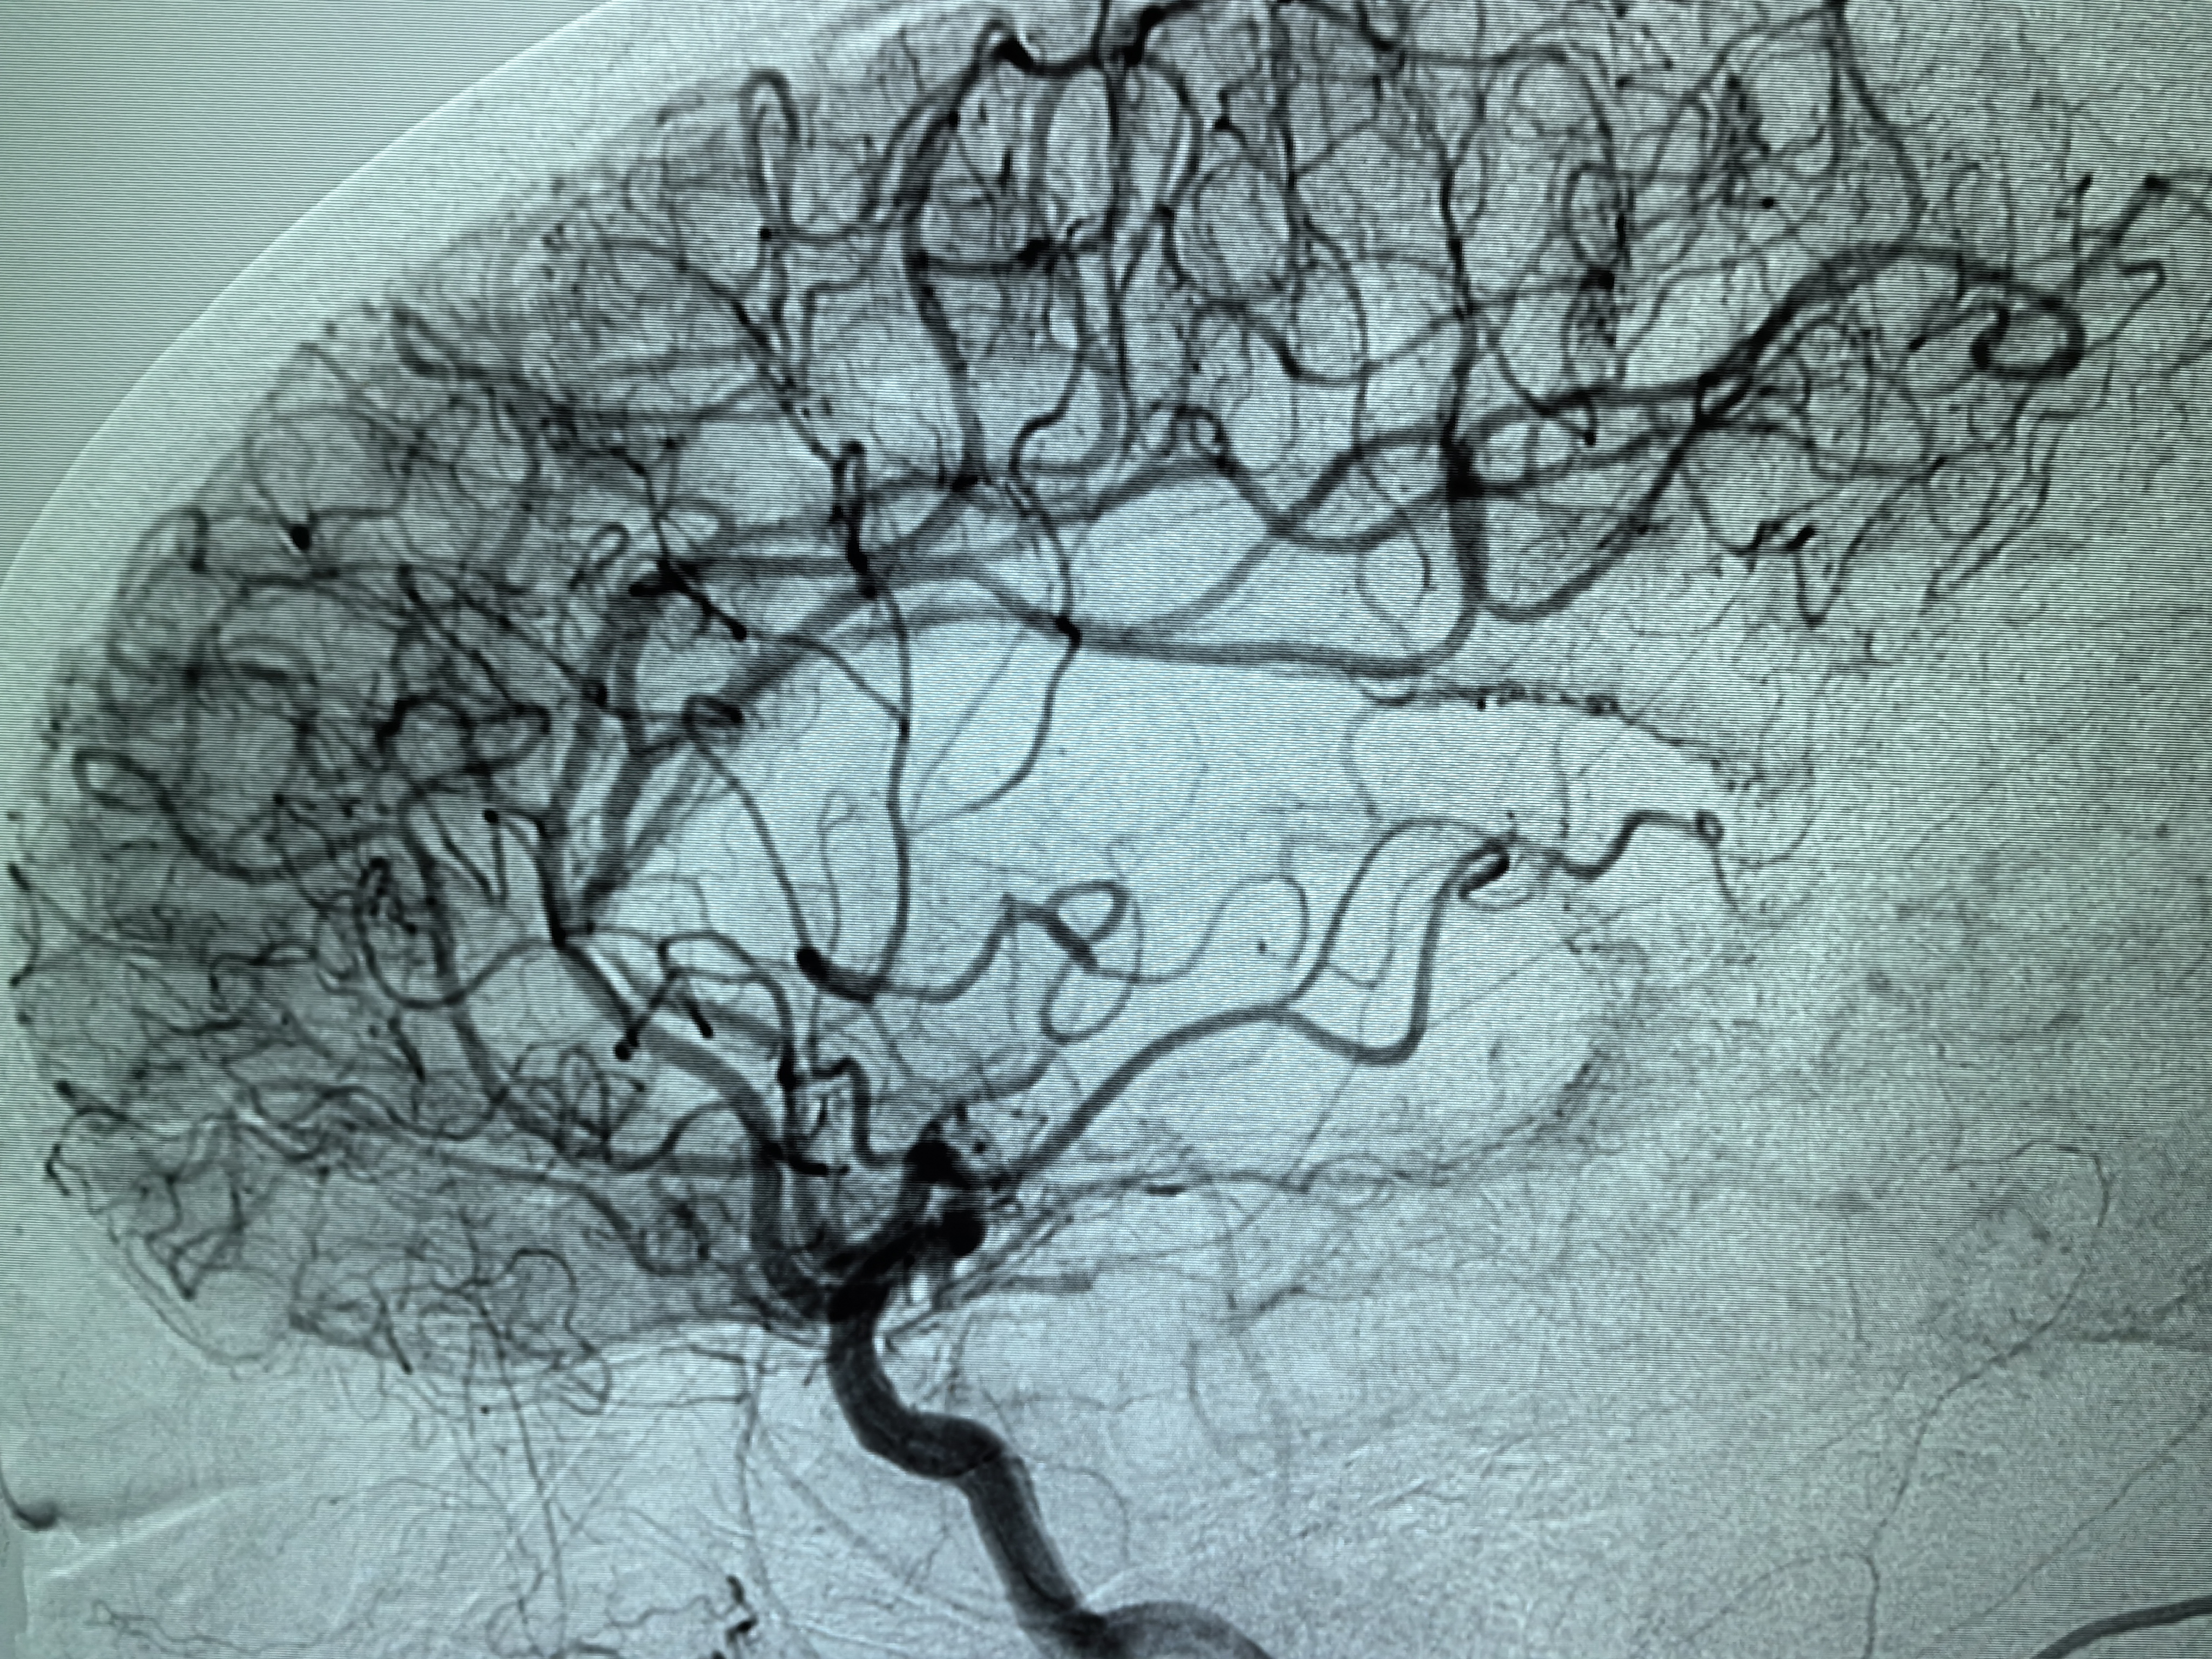

1、本例患者老年女性,系骨科术后次日醒后卒中,经核磁评估提示左侧大脑中动脉闭塞,系责任血管,患者心电图示房颤,考虑心源性栓塞可能性大。

2、本例患者SWIM技术取栓一次后血管再通,颅内血流通畅。